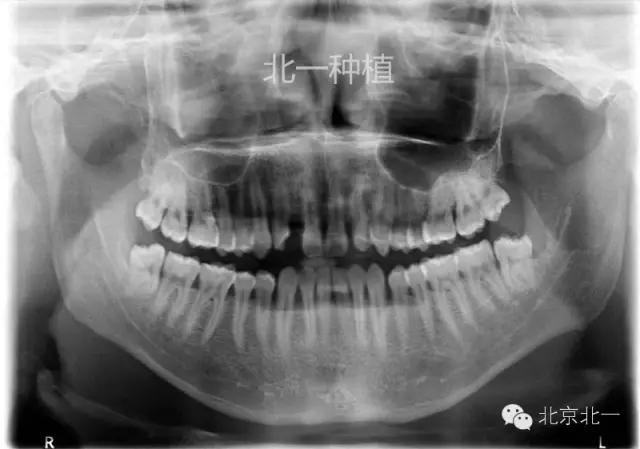

手術(shù)前拍CBCT及全景片、右上中切牙根尖高密度印象。

手術(shù)后拍全景片,順便把滯留乳牙拔除了。